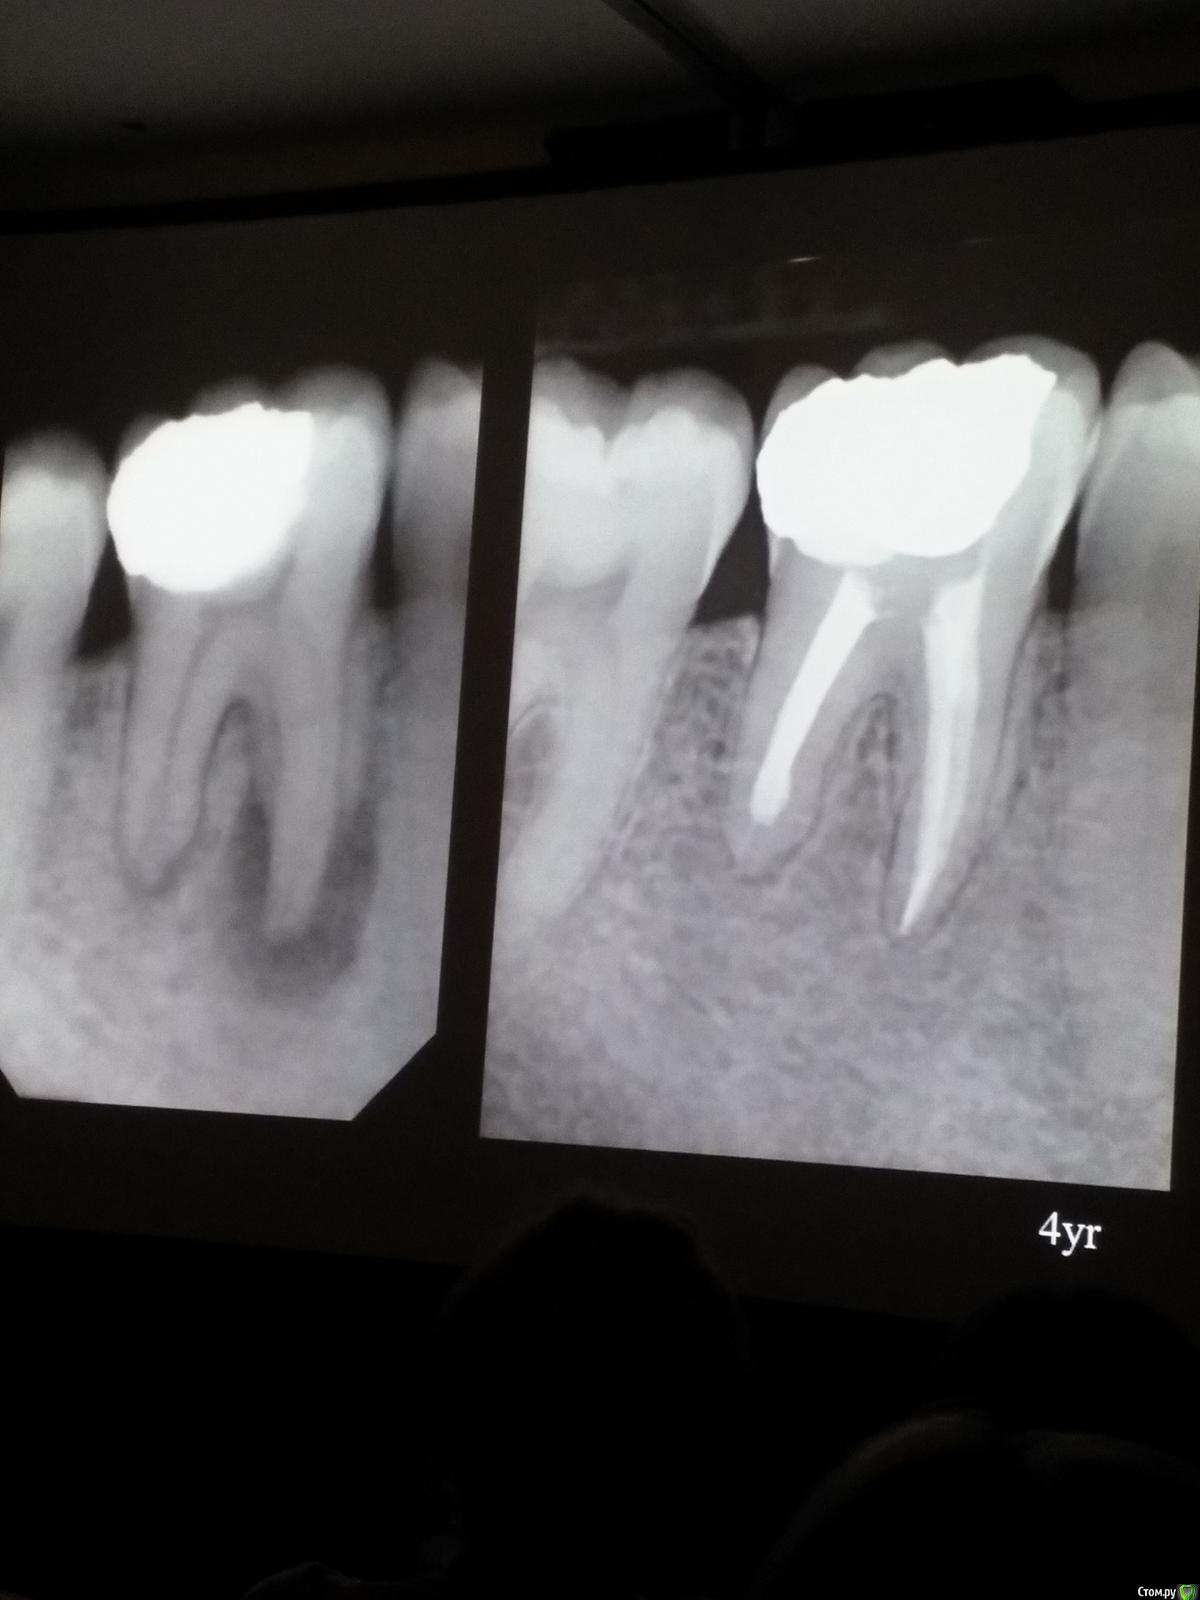

Популярный пост Kolchanov Опубликовано 11 марта, 2017 Популярный пост Поделиться Опубликовано 11 марта, 2017 (изменено) Товарищи, скажу я вам...........Вкратце. Может я где-то что-то и приврал, надеюсь, кто еще был, поправят. Честно говоря немного прибалдел от уровня Доктора. Очень, очень высоко! Приедет еще раз, пойду еще. 1) Фиссуры зондирует острым зондом и выпиливает все дотла. По факту у него уже пломбы, а не герметизация.2) Bite-wing у первичных пациентов всегда.3) Если кариес диагносцирован, то лечить его, пофиг какой он там. Эмали, дентина…4) Препарирует до твердого (или до вскрытия J ). CAD, СID… в топку. Кариес маркером не пользуется, проверяет острым зондом/экскаватором. Вычищает все дотла. Считает, что даже небольшое количество бактерий в дентине под пломбой вызывают хроническое воспаление в пульпе. С его слов у него на контроле где-то 500 вскрытий, не удивительно при таком подходе к очистке.5) Тщательная изоляция. Коффер порвался – меняет. Большое значение герметичности реставрации. под замену6) Критерии обратимости и необратимости.Гистологически, обратимый тот, что без абсцессов в пульпе, но клинически это понять нельзя, только предположить.Здесь был бы обратимый, если бы не удалил. Нет микробов в пульпе. Линия - граница обработки.Покрытие 27 лет назад. Dycal, СИЦ, композит. От дайкала одно воспоминание.7) Вскрылись. Размер перфорации, возраст и прочее не играют роли, важно только состояние пульпы, т.е. диагноз.Примеры перфораций.8) Кровотечение останавливает стерильным ватным шариком. Если останавливается, то покрытие, если нет, то пульпотомия или пульпэктомия.9) Использует гидроокись кальция (порошок), перекрывает Dycal или СИЦ. Потом восстановление Нередко под IRM, потом все убирает (через пару-тройку месяцев) и смотрит, что получилось. Порой приходится повторять! Использует и МТА, его тоже убирает.10) Наблюдение 6мес, 1 год, 2…. Все может провалиться и через месяц и через 24 года.Примеры проваловНиже - 24 года спустя появилась дуля. 11) Неравномерная облитерация полости зуба на RG (после покрытия) – признак текущего хронического воспаления, где-то остались микробы. Рекомендует эндо.12) Мостик который образуется – это не дентин! И одонтобласты не регенерируют и новые не образуются. Что это такое он и сам не знает, но раз это твердые ткани, то и наплевать.Вот фиолетовое это дентинные опилки вмурованные в розовую ткань бог знает кем сформированную.13) Пульпотомия в зубах с несформированной верхушкой и в сформированных, при подозрении на частичное поражение коронковой пульпы. Иссекается стерильным алмазным бором часть пульпы, гидроокись, временная пломба на 90 дней, после повторное раскрытие, оценка результата, восстановление в случае формирования твердых тканей. Гипохлоритом можно мыть, можно не мыть, если мыть, то 0,5-1%.14) В апикальной части пульпа чаще витальна, чем нет.15) Периапикальные поражения возникают по причине поступления токсинов микробов с током крови, а не самих бактерий.16) За апикальные расширения в полностью некротических случаях. Надо механически отодрать биопленку и срезать инфицированный дентин. На ирриганты надежды мало.17) Биопленка на поверхности в 6% случаев.Синенькие пид@расы18) Обработку проводить нежно, краун-даун. Чередовать с H-файлом, чтобы посмотреть докуда распространяется некроз.19) Патенси в витальных кейсах не колоть, сохранять витальную пульпу в констрикции!Формирование еще большего сужения в констрикции за счет сохранения витальной пульпы. Изменено 11 марта, 2017 пользователем Kolchanov 31 Ссылка на комментарий

Популярный пост Kolchanov Опубликовано 12 марта, 2017 Автор Популярный пост Поделиться Опубликовано 12 марта, 2017 Второй день.1) Дезинфекция зуба и раббер дама перед работой. Вначале установка системы, потом протирка тампоном 30% перекиси, потом протирка всего йодинолом. Потом преп, потом повторение и только потом доступ к к/к. Все старые реставрации надо убрать, кариес убрать, противник лечения через коронку.2) Гидроокись на неделю. Замешивает на стерильном физрастворе. При необходимости повторяет. Т.е. в случае сохранения свища, симптоматики, экссудации, запаха. Если свищ не исчезает после трех смен временных вложений, то хирургия.3) Пломбирует латеральной компакцией. Лучше контроль длины обтурации.4) Высушивание канала стерильными штифтами, на рабочую длину минус 1мм. После высушивания штифт оставляется на 60с. в канале и должен выйти сухим.5) Определение рабочей длины. Витальные случаи. АЛ должен три раза дать одну и ту же картинку в определенной точке + проверка RG. Девитальные случаи. На АЛ полагаться сложно, т.к. из-за наличия резорбции констрикции может врать, больше ориентируется на RG.6) Использует ЦОЭ силеры. Резорбируются при незначительном выведении. Резорбируются в канале, позволяя закрыть апекс цементоподобной тканью. Вот так вот.Случаи исчезновения силера, как за пределами канала так и в канале7) Выведение материала (не важно какого) в большом объеме способно вызвать защитную реакцию тканей. Которая должна пройти спустя некоторое время. (иногда это будет 25 лет J Случай 1ый. Студенты наломали инструментов. Периодонтит на RG через год. Резекция и гистология. Бактерий не обнаружил. Да, маленькое замечание. Каждый препарат дает 500-600 срезов. И ищет он на всех. Объем работы, конечно….Случай 2й. Его собственный. Периапикальное поражение, обнаруженное на реколле через 10 лет зажило еще через 15.8) «Функционирующий зуб» считает результатом неприемлемым. Осталась инфекция с которой надо что-то делать. То, что бактерий можно замуровать в дентинных трубочках и под пломбировочным материалом, считает неправильным. Продукты метаболизма один фиг будут просачиваться и могут поддерживать реакцию воспалительную.Случай. Синее – маленькая кучка микробов, предположительно, препятствовавших заживлению очага.9) Биопленка на поверхности корня может принимать вид кальцификатов (камней) и тут уже только хирургия в помощь. При длительном существовании свищевого хода, например.Черное - это камни вокруг апикального отверстия. И гистология их с кучей синих микробов.Здесь камни на фуркации и отсутствие заживления и свищ даже после ретроградной обработки и пломбировки.А здесь вообще чертова уйма камней. И зацените разветвление канала в этом боковом резце (последнее фото препарата). 10) Реваскуляризация.В некротических случаях дентина не образуется, т.к. одонтобластов нет и не будет новых. Образуется та самая бог знает какая ткань, которая даже и с корнем не связана может быть. Суть здоровый дентикль-петрификат. А в витальных это не реваскуляризация, а обычное формирование корня. Так что нечего тут.11) Трещины дентина.Советует расшивать, братья и сестры. Без фанатизма, если нет симптоматики, но, по возможности максимально. Если есть симптоматика, то там уже по обстоятельствам. Чертова уйма микробов там и ползет, ползет к пульпе. Надеюсь, что еще раз этот замечательный Доктор приедет. Схожу с удовольствием. 2 23 Ссылка на комментарий